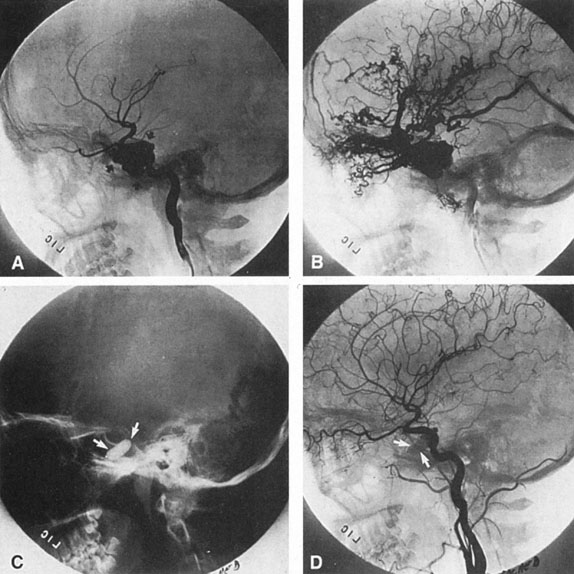

The detection of intracranial AVMs is facilitated by CT scanning and MRI (Fig. 10),88 but optimal management requires selective angiography89 that assesses the size and configuration of the mass, the number and location of feeding arteries, the flow characteristics and degree of steal from brain parenchyma, and the pattern of venous drainage.

Fig. 10. Neuroimaging of arteriovenous malformation. A: Coronal magnetic resonance imaging (MRI) (TR, 600 ms; TE, 20 ms) shows wedge-shaped vascular mass extending from the surface of the parietal cortex (white arrows) to the lateral ventricle (black arrows; asterisk, arterial feeder). B: Posteroanterior left arteriogram of the same lesion. C: Axial computed tomography scan with contrast enhancement. D: Axial MRI of a large arteriovenous malformation, first echo (TR, 2000 ms; TE, 20 ms). E: Second echo (TR, 2000 ms; TE, 90 ms). (From Smith HJ, Strother CM, Kikuchi Y, et al: MR imaging in the management of supratentorial intracranial AVMS. AJNR Am J Neuroradiol 9:225, 1988.)

The therapy for AVMs has been reviewed elsewhere.91–93 The preferred treatment remains complete surgical excision of the malformation. However, significant advances in endovascular and radiosurgical techniques have resulted in a marked increase in the use of multimodal, staged approaches to AVM treatment. A variety of intravascular techniques use embolization91 with materials such as particles of polyvinyl alcohol (PVA), platinum coils, and injection of liquid N-butyl-cyanoacrylate (NBCA) adhesive (Fig. 11). Complications of intravascular embolotherapy include vessel perforation by the catheter, migration of embolic materials, and infarction and hemorrhage of normal brain.

Fig. 11. Embolization of middle cerebral vessels that supply occipital lobe arteriovenous malformation (AVM). The patient had a subarachnoid and intraparenchymal hemorrhage that produced a left homonymous field defect. A: Right carotid arteriogram demonstrates contribution via posterior communicating artery to a right occipital lobe AVM. B: Vertebral injection. The arrow points to the enlarged right posterior cerebral artery that is a major feeder of the AVM. C: Right carotid arteriogram during glue embolization procedure. The arrow points to a catheter as it traverses the segment seen in (B). The catheter was advanced via the internal carotid artery but is positioned far posteriorly. D: Upper branches to the AVM now are occluded, with residual low-flow vascularization via the middle cerebral artery. E: Skull film showing radiopaque glue within the AVM and blood vessels previously supplying it. The patient had a persistent visual field defect but greatly reduced headache and no persistence of subjective bruit. (Courtesy of Dr. Joseph Horton.)